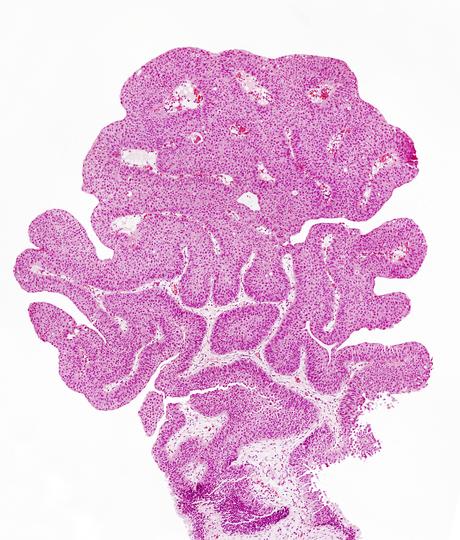

L'immunothérapie post-chirurgie permet de réduire le risque de récidive

du cancer urothélial de la vessie ou d'autres sites des voies urinaires, s’étant déjà propagé au muscle et posant donc un risque élevé de récidive, confirme cette étude. Ces résultats appuient l'administration de l'immunothérapie nivolumab comme traitement adjuvant après la chirurgie et appellent à adopter cette nouvelle norme de soins pour les patients atteints d'un carcinome urothélial invasif musculaire.